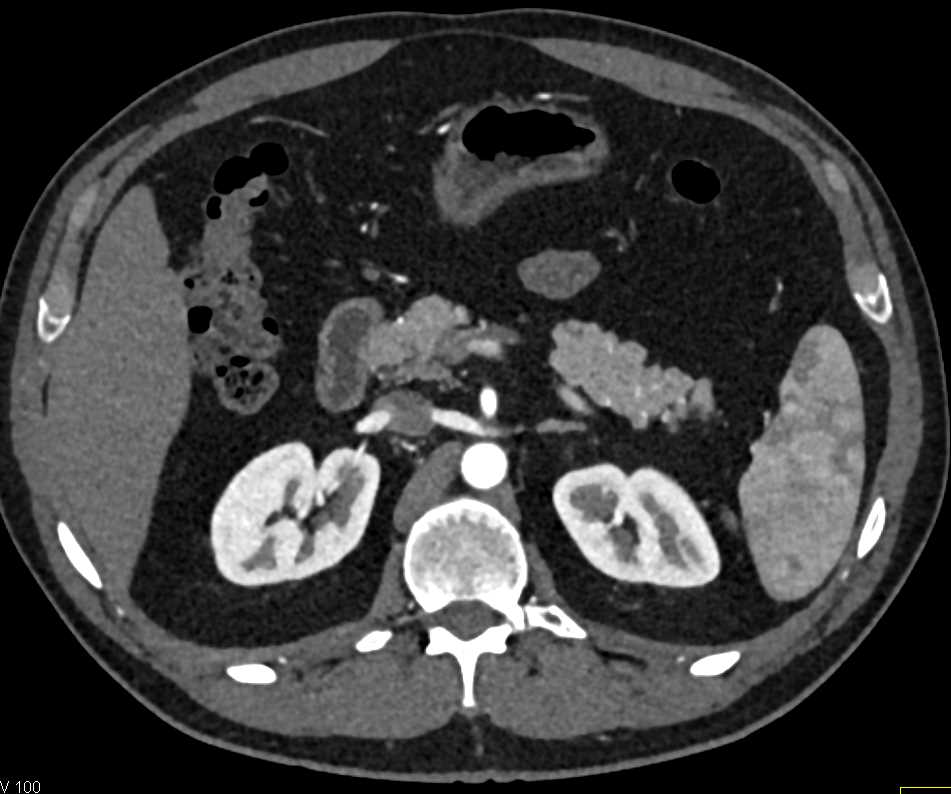

Neuroendocrine Tumor Body of Pancreas